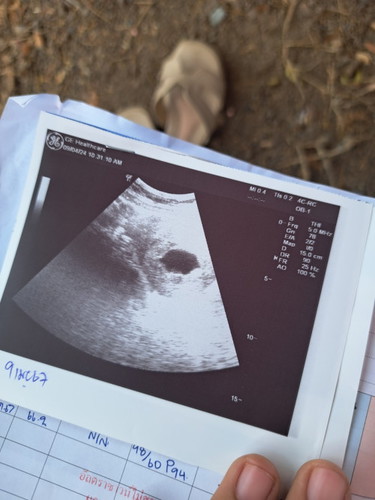

บ้านไหนเป็นบ้างคะ8+3wแล้ว ยังไม่เจอตัวน้องเลยค่ะ เจอแต่ถุง แล้วมีมูกเลือดออก หมอสันนิตฐานว่าจะท้องลม นัดไปคอนเฟิร์มอีกที12w ใจไม่ดีเลยค่ะ ท้องแรก6+5wซาวก็เจอตัวน้องแล้วค่ะ

ของเราซาว 9w ไม่พบน้องเหมือนกันคะ หมอนัดไปซาวอีก3สัปดา ท้อง 2 ท้องแรก10wซาวเป็นตัวดิ้นแล้ว แอบกังวลเหมือนกันคะ แต่ไม่ทีเลือดออกหรืออะไรนะคะ

ของเรานับประจำเดือนได้13w แต่นับตามใบซาวได้9wเองค่ะตอนนี้ อายุครรภ์ไม่ต้องค่ะ หมอให้เอาในใบซาวเป็นหลัก

ท้องที่ 2ตอนซาว 8+3ไม่พบตัวน้องเหมือนกันค่ะ ตอนซาวรอบ 2 หมอขอบอกว่าท้องนอกมดลูกต้องผ่าตัดออกค่ะ

ของเราหมอบอกว่าท้องในมดลูกค่ะ แต่ไม่แน่ใจว่าจะท้องลมไหม รอคอนเฟิร์ม12wค่ะ

หมอบอกเห็นถุงตั้งครรภ์อย่างเดียวค่ะ ของเรานัด2พค.เลย